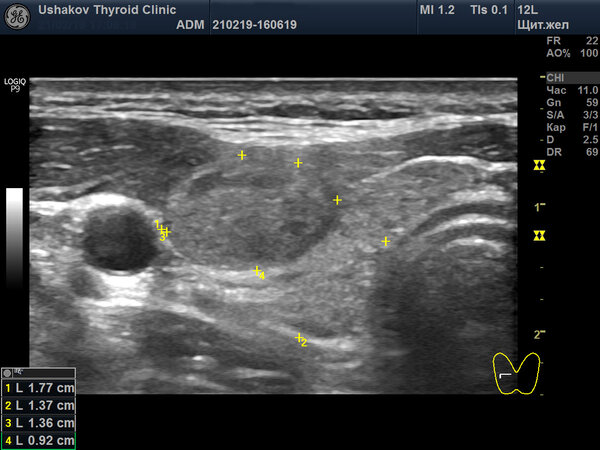

Пример качественного протокола УЗИ щитовидной железы

Для сравнения предлагаем ознакомиться с протоколом, составленным в нашей клинике. Исследование проведено у того же пациента спустя две недели после предыдущего.

Это лишь два снимка из двенадцати, которые были приложены к протоколу. На практике мы распечатываем для пациента от 6 до 25 высококачественных изображений, демонстрирующих все ключевые особенности состояния железы.